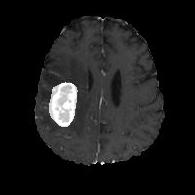

We argue that the sub-optimal paradigm of processing different abstractions within a single CNN pipeline can be remedied through the effective processing of information in a structured manner. Consequently, we devise strategies for disentangling the edge and texture information within a single training pipeline. Figure 2 illustrates how our proposed module, dubbed EG-CNN, can be paired with any existing CNN encoder-decoder to improve segmentation quality near intensity edges. We have applied our EG-CNN to the tasks of brain and liver tumor segmentation in medical images (Figure 3).

(1) Brain MR (2) Liver MR (3) Liver CT (4) Lung CT